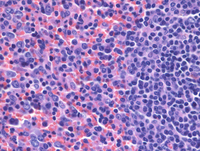

Spleen involvement by JMML

The splenic red pulp shows extensive involved by the same atypical mononuclear infiltrate with increased monocytes. The image on the is notable for a nodule of unremarkable white pulp present on the right side of the image.